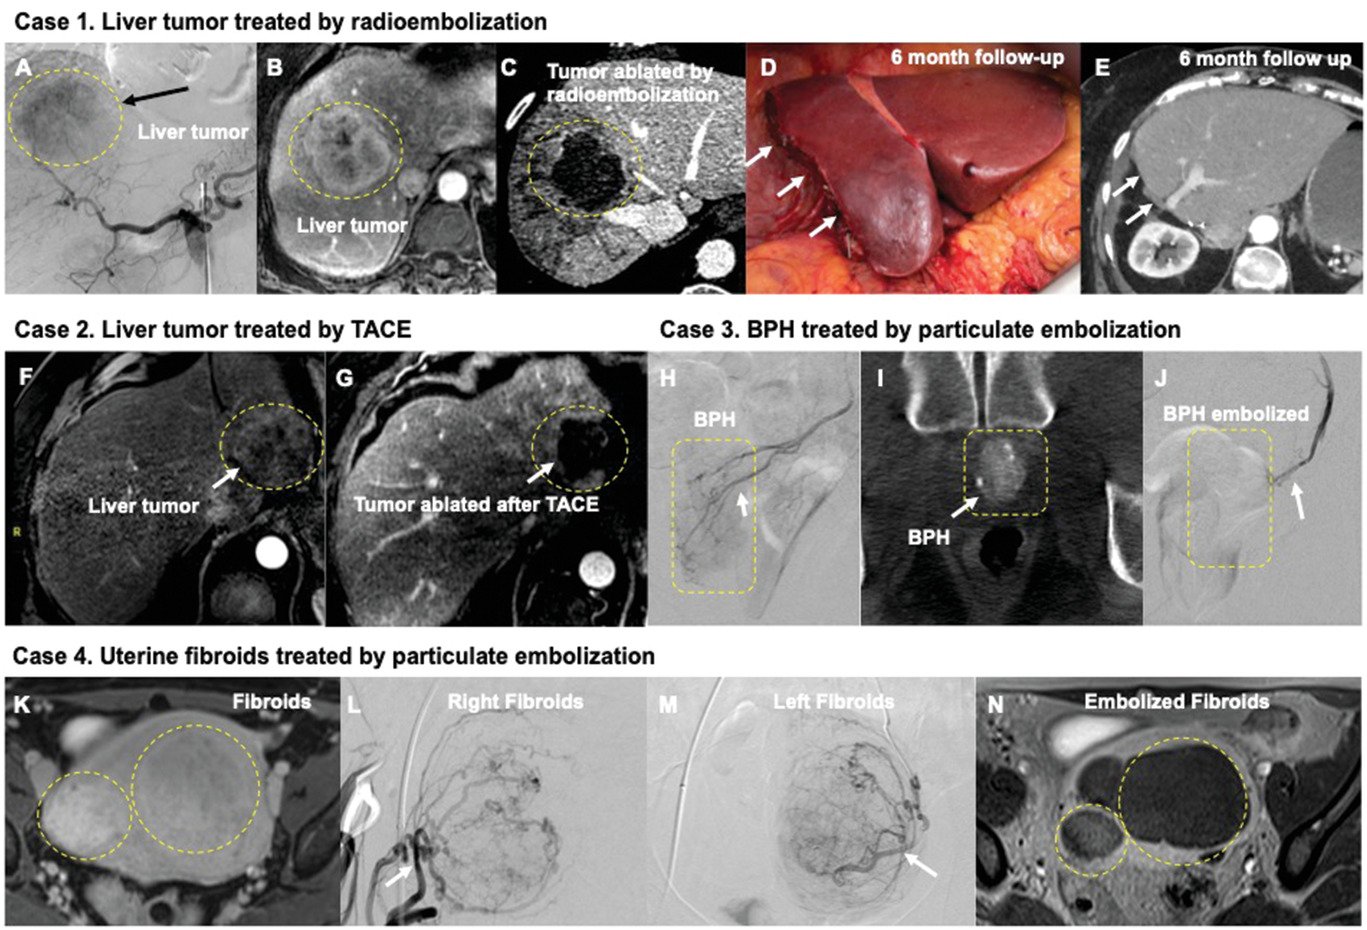

Radioembolization, also known as Y-90 radioembolization, is a minimally invasive procedure that involves the injection of tiny microspheres into the artery that supplies blood to your liver — and ultimately, to your tumor. As the particles travel from the entry site in your groin through the liver, they block off (or embolize) blood flow to the tumor and prevent it from receiving any further nutrients from your body

Radioembolization Y-90 Farmington is a procedure that delivers radio-labeled particles to a tumor. This treatment can be used when other treatments have not been successful or when cancer has spread to the liver from other parts of the body. The particles are inserted into a vein and travel through your body until they get to where they’re needed most — stopping cancer cells from growing and multiplying as fast as before. It’s also known as Selective Internal Radiation Therapy (SIRT). In some cases, this procedure can be combined with chemotherapy or surgery.

Radioembolization Y-90 Farmington is a technique used to treat liver cancer or tumors that are not amenable to surgery and have begun to invade other organs or structures. The process starts with imaging scans called a CT or MRI scan of your body which act as a map and help pinpoint abnormal tissue growths. A substance called yttrium-90 is injected into the blood vessels supplying your tumor(s). This releases radiation into your liver tumor, which destroys it by damaging its cells and tissues. The substance travels throughout your body and deposits its radioactive particles in any areas where disease may exist causing damage to diseased tissue nearby.

Radioembolization Y-90 is a minimally invasive procedure that can treat liver cancer by injecting radioactive materials into blood vessels to block the flow of blood and oxygen to tumors. This may cause tumors to shrink or disappear altogether and result in reduced symptoms like pain or jaundice and improved quality of life.